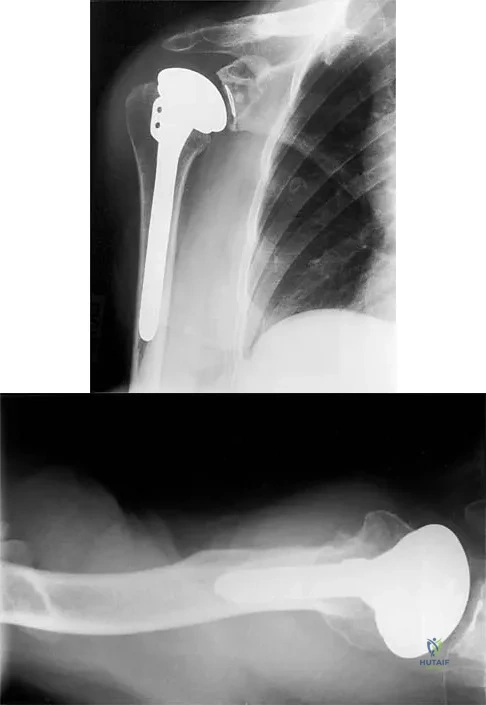

Question 37

A 54-year-old man undergoes total shoulder arthroplasty for osteoarthritis. Despite compliance with an early passive range-of-motion exercise program, he does not regain more than 90 degrees of elevation, 10 degrees of external rotation, and has internal rotation to the fifth lumbar vertebra. At 6 months, his motion fails to improve. Radiographs are shown in Figures 18a and 18b. What is the best course of action?

Explanation